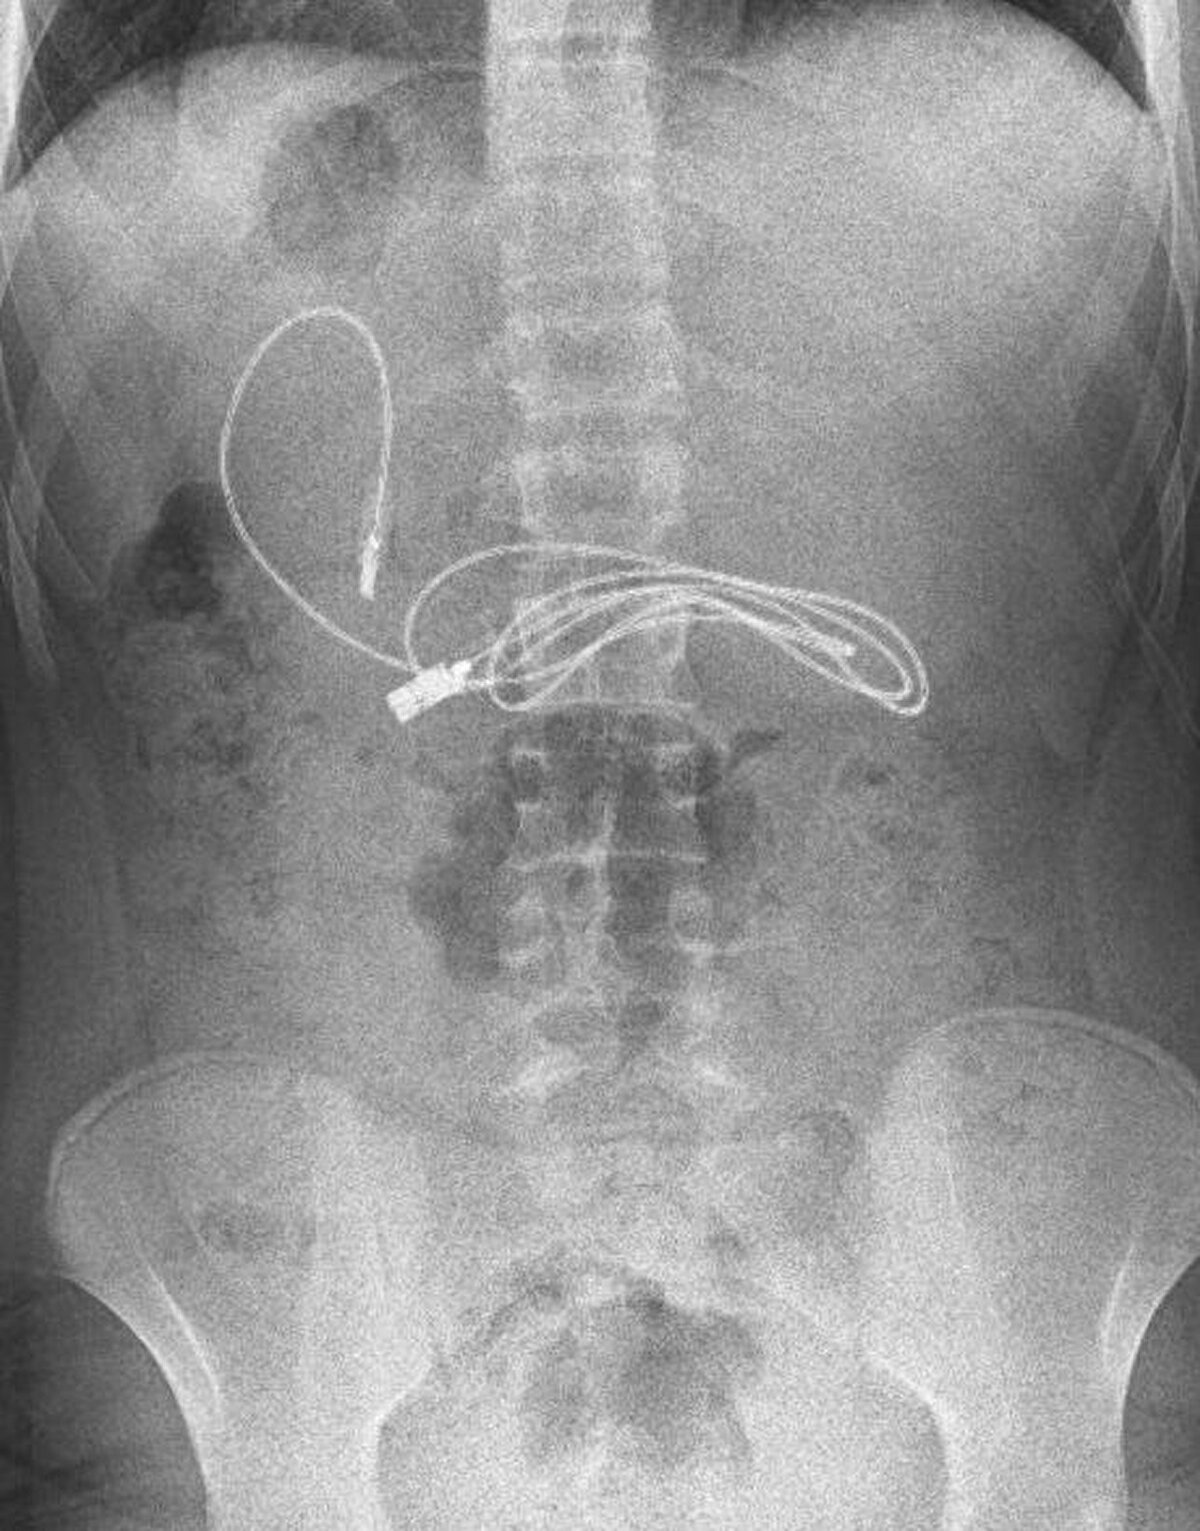

Diyarbakır'da kusma ve bulantı şikayetiyle hastaneye götürülen, çekilen röntgeninde 1 metrelik şarj kablosu ve toka yuttuğu tespit edilen 15 yaşındaki erkek çocuğu, Elazığ'da gerçekleştirilen operasyonla yuttuğu cisimlerden kurtuldu.

Diyarbakır'da kusma ve bulantı şikayetiyle ailesi tarafından hastaneye götürülen erkek çocuğunun çekilen röntgeninde, midesinde şarj kablosu ve toka olduğu tespit edildi.

Bunun üzerine çocuk, ambulans ile Fırat Üniversitesi Hastanesi'ne sevk edildi. Üniversitenin Çocuk Gastroenteroloji Hepatoloji ve Beslenme Bilim Dalı Başkanı Prof. Dr. Yaşar Doğan ve ekibi tarafından yapılan endoskopik işlemle çocuğun midesindeki kablo ve toka başarıyla çıkarıldı. Tedavisinin ardından sağlığına kavuşan çocuk taburcu edildi.

Ameliyatı gerçekleştiren Prof. Dr. Yaşar Doğan, kablonun bir ucunun ince bağırsağa geçmesi nedeniyle zorlandıklarını ifade ederek, “Hastanın kusma ve karın ağrısı şikayetleri olması üzerine sağlık kuruluşuna başvurulmuş. Orada yapılan incelemelerde hastanın midesinde kablo tespit edilmesi üzerine bize danışıldı.